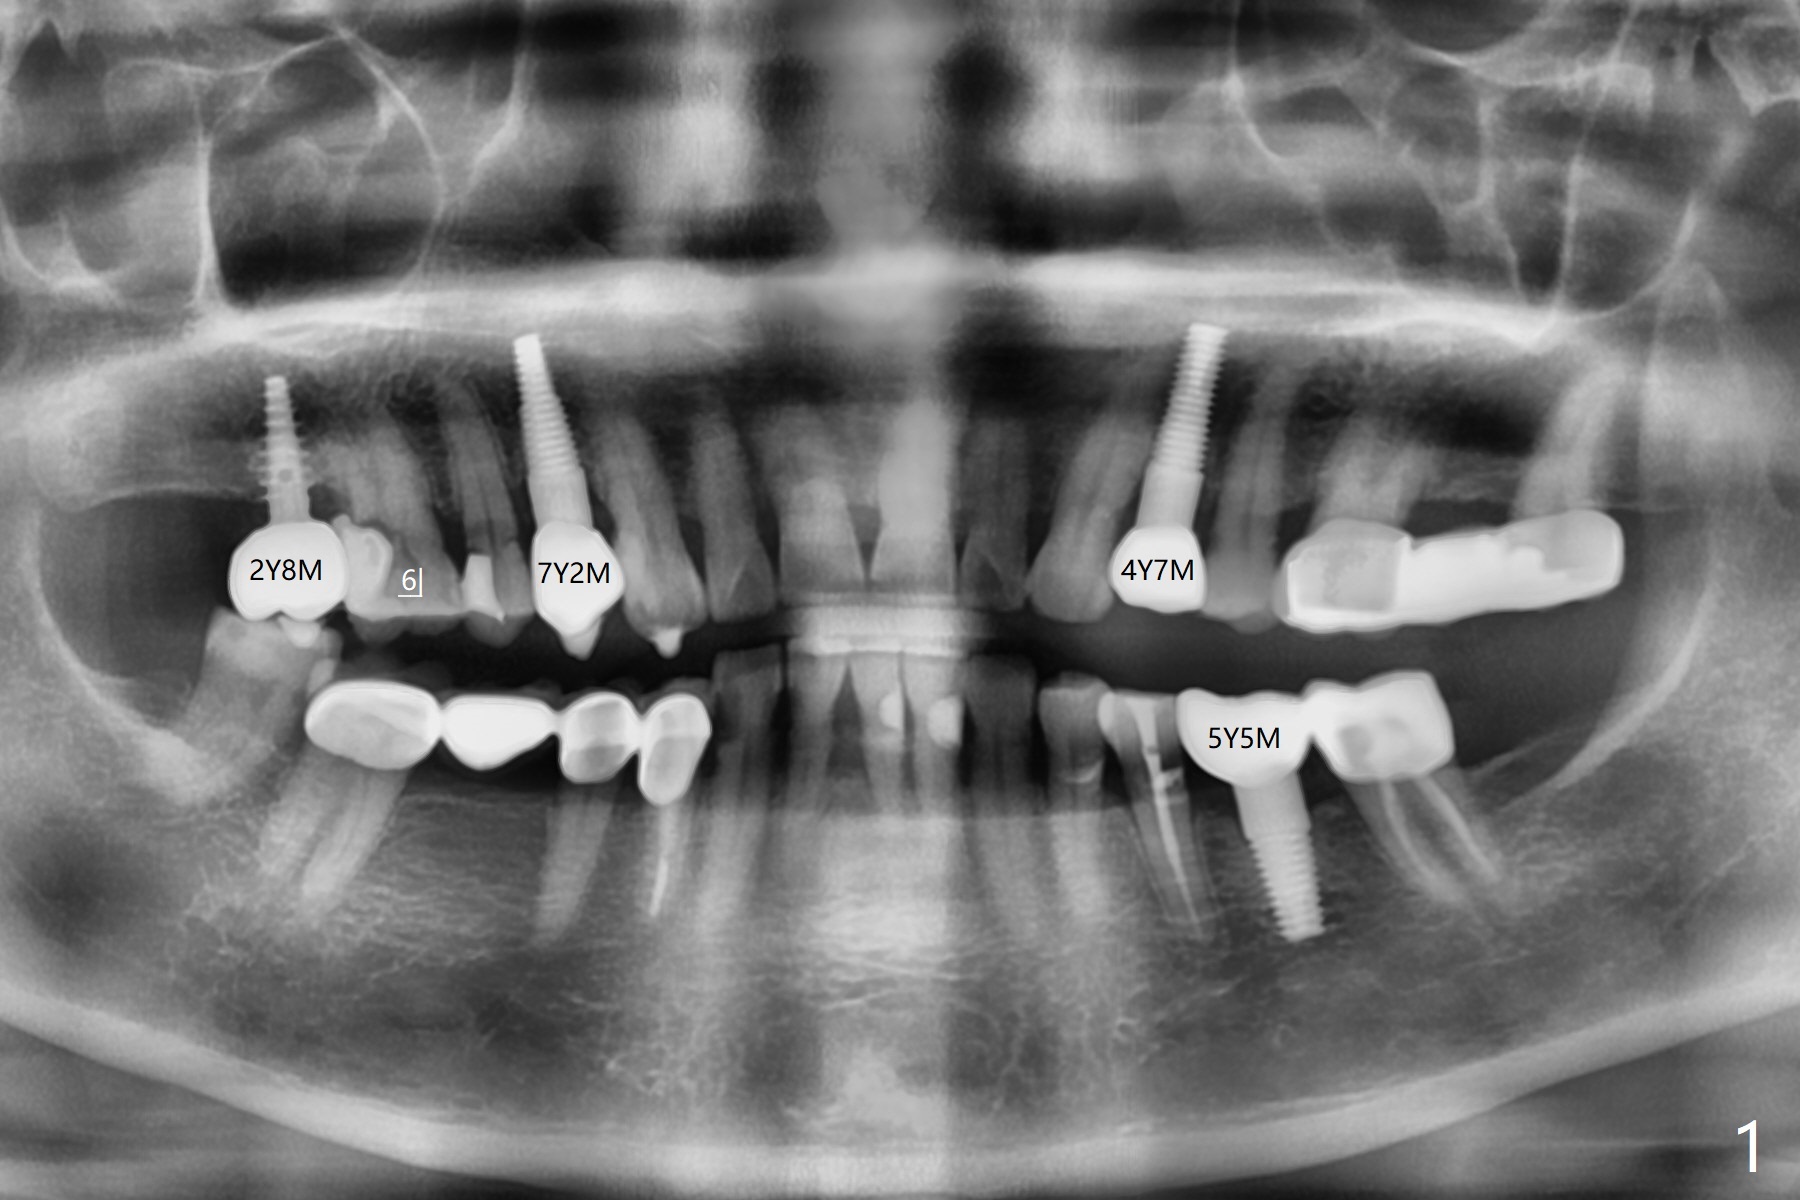

63岁女右上6远中龋齿在邻牙植牙牙冠粘固后2年8个月坏的严重(图一),病人决定拔除种植。之前嘱咐她回来修复,部分由于新冠病毒,她拖延治疗。今后需要建立一个植牙后完整随访和严密检查系统,减少继发龋。分析四个植牙(图二,四至六)表明骨质宽度优越,右上6即刻种植应该没问题(图三)。植体选择与邻近一致。Prevent Molar Periimplantitis (Protocols, Table) No Neighboring Caries Metronidazole Magicore Cases 手术 2 Xin Wei, DDS, PhD, MS 1st edition 10/14/2020, last revision 11/17/2020